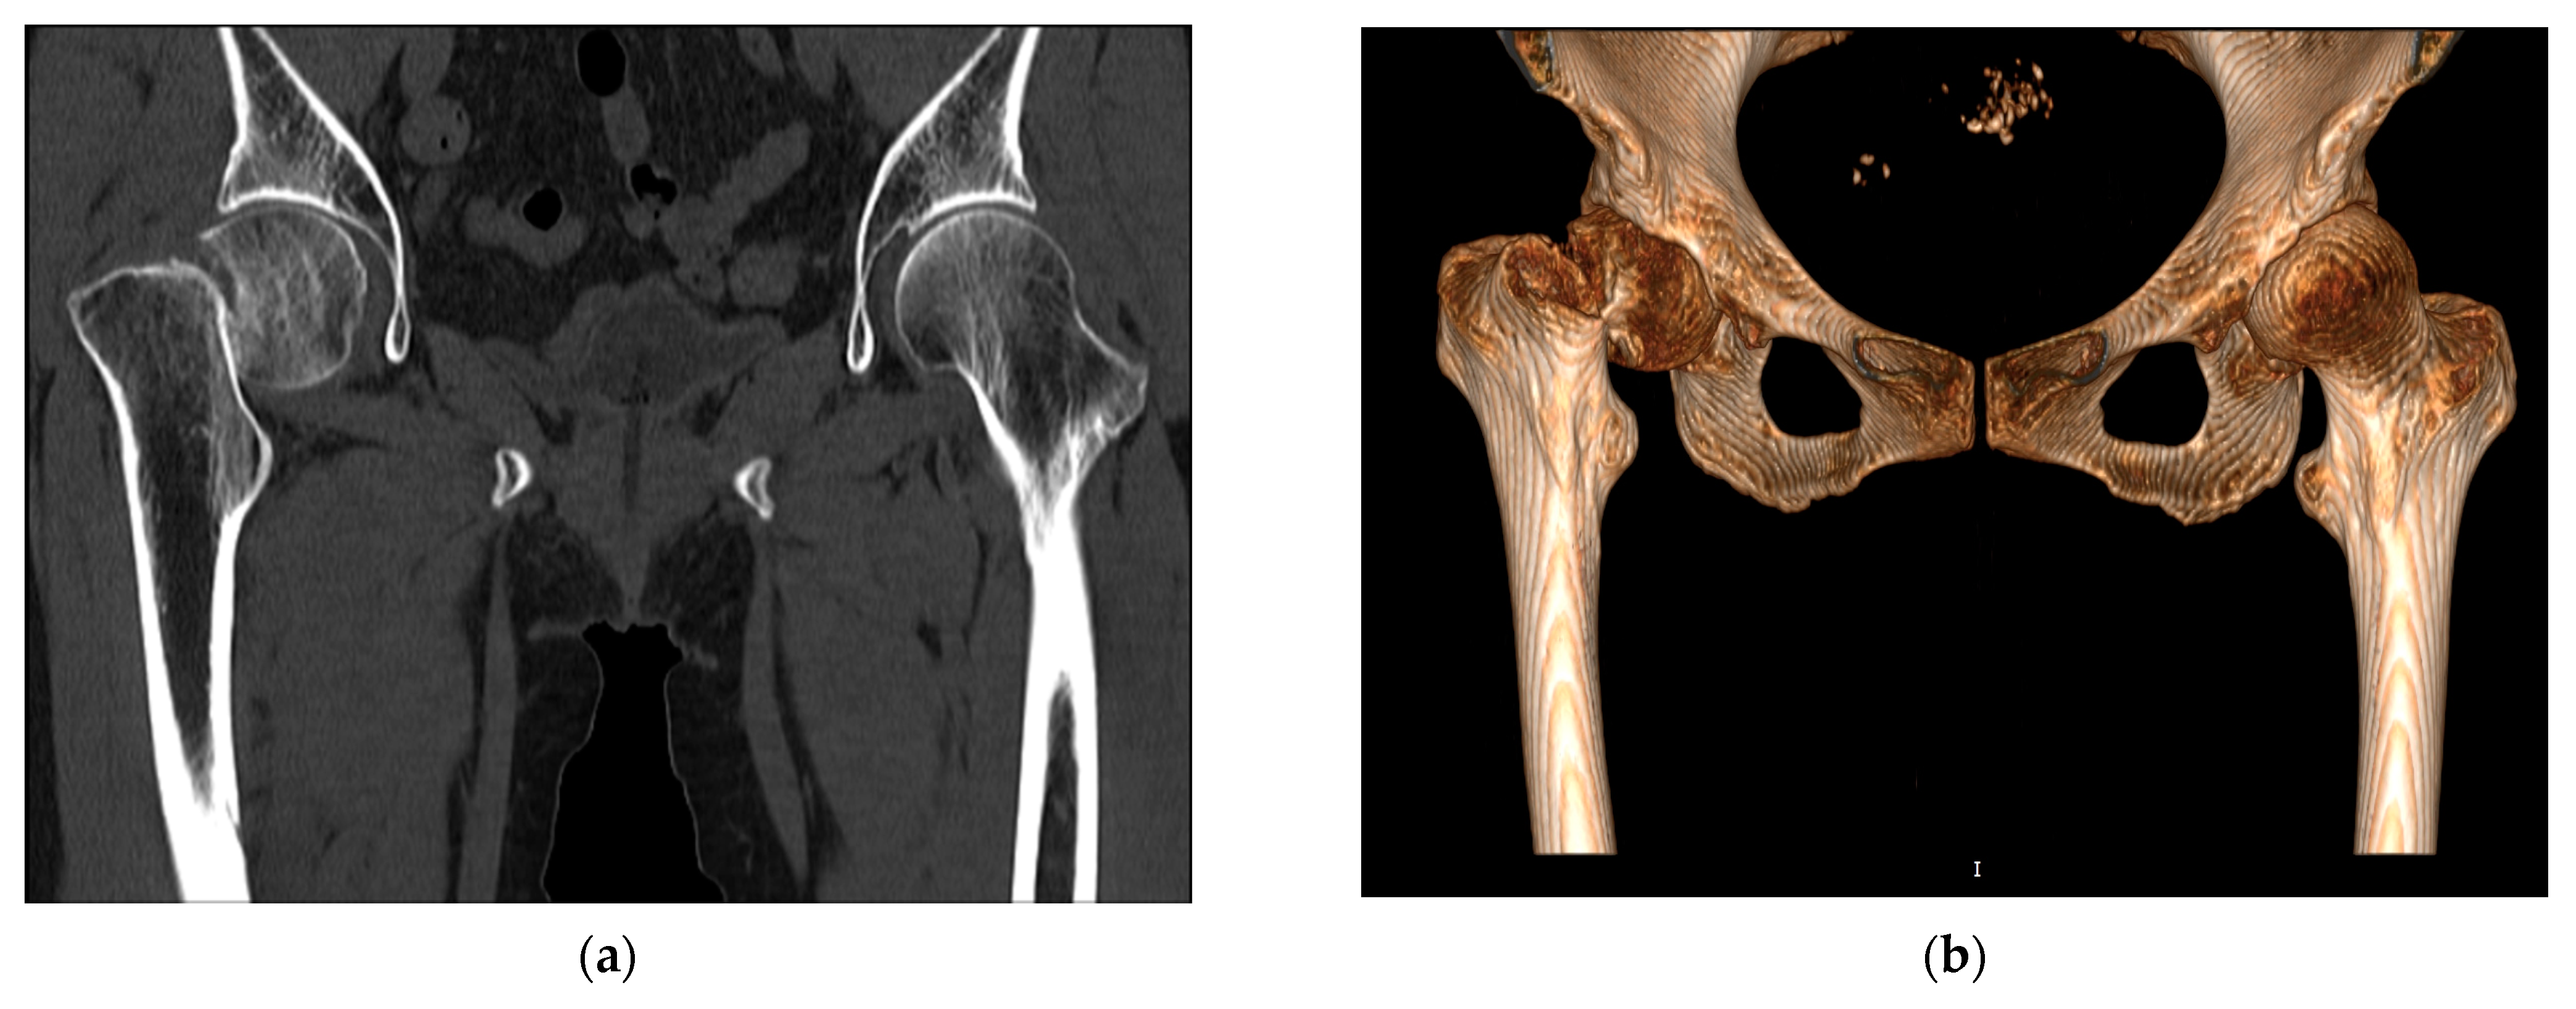

We analyzed 10 cases from March 2012 to January 2015 provided by Hyogo Prefectural Awaji Medical Center. All the cases were associated with intracapsular fracture and the age of the patients ranged from 65 to 85. As shown in Figure 1, an intracapsular fracture refers to the femoral neck fracture that occurs within the capsule of the hip joint.

Figure 1. Intracapsular fracture occurring because of low-energy falls in the elderly: (a) CT diagnostic image; (b) 3D reconstruction model.